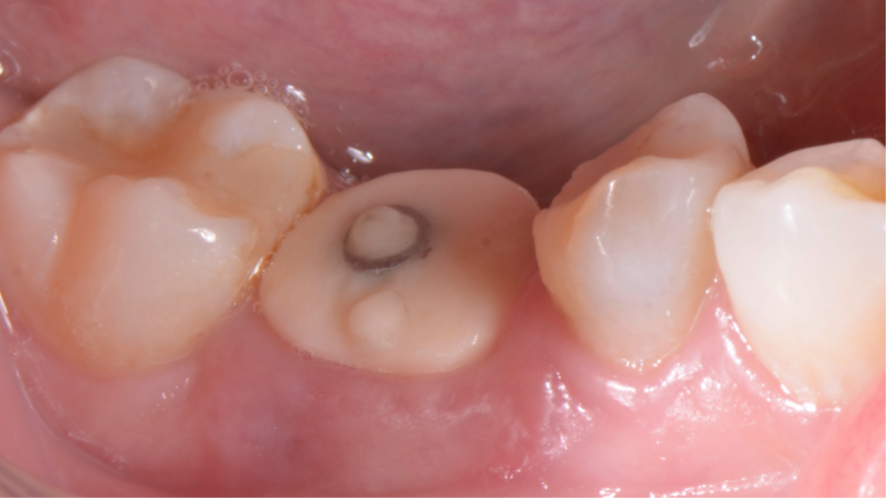

Mulher de 48 anos, sem antecedentes médicos relevantes, procurou atendimento odontológico com queixa principal de dor contínua em região do primeiro molar inferior direito. Na avaliação clínica foi observado uma fístula na vestibular do dente 46 (Figura 1) e a tomografia revelou uma fratura longitudinal, comprometendo a manutenção deste dente (Figura 2). Confirmada a necessidade de exodontia, foi planejada a instalação de um implante imediato e a confecção de um cicatrizador personalizado diretamente na plataforma do implante com um pilar provisório de titânio. Foi realizada uma extração dentária minimamente traumática visando preservar a integridade dos tecidos moles e duros circundantes (Figuras 3 e 4).